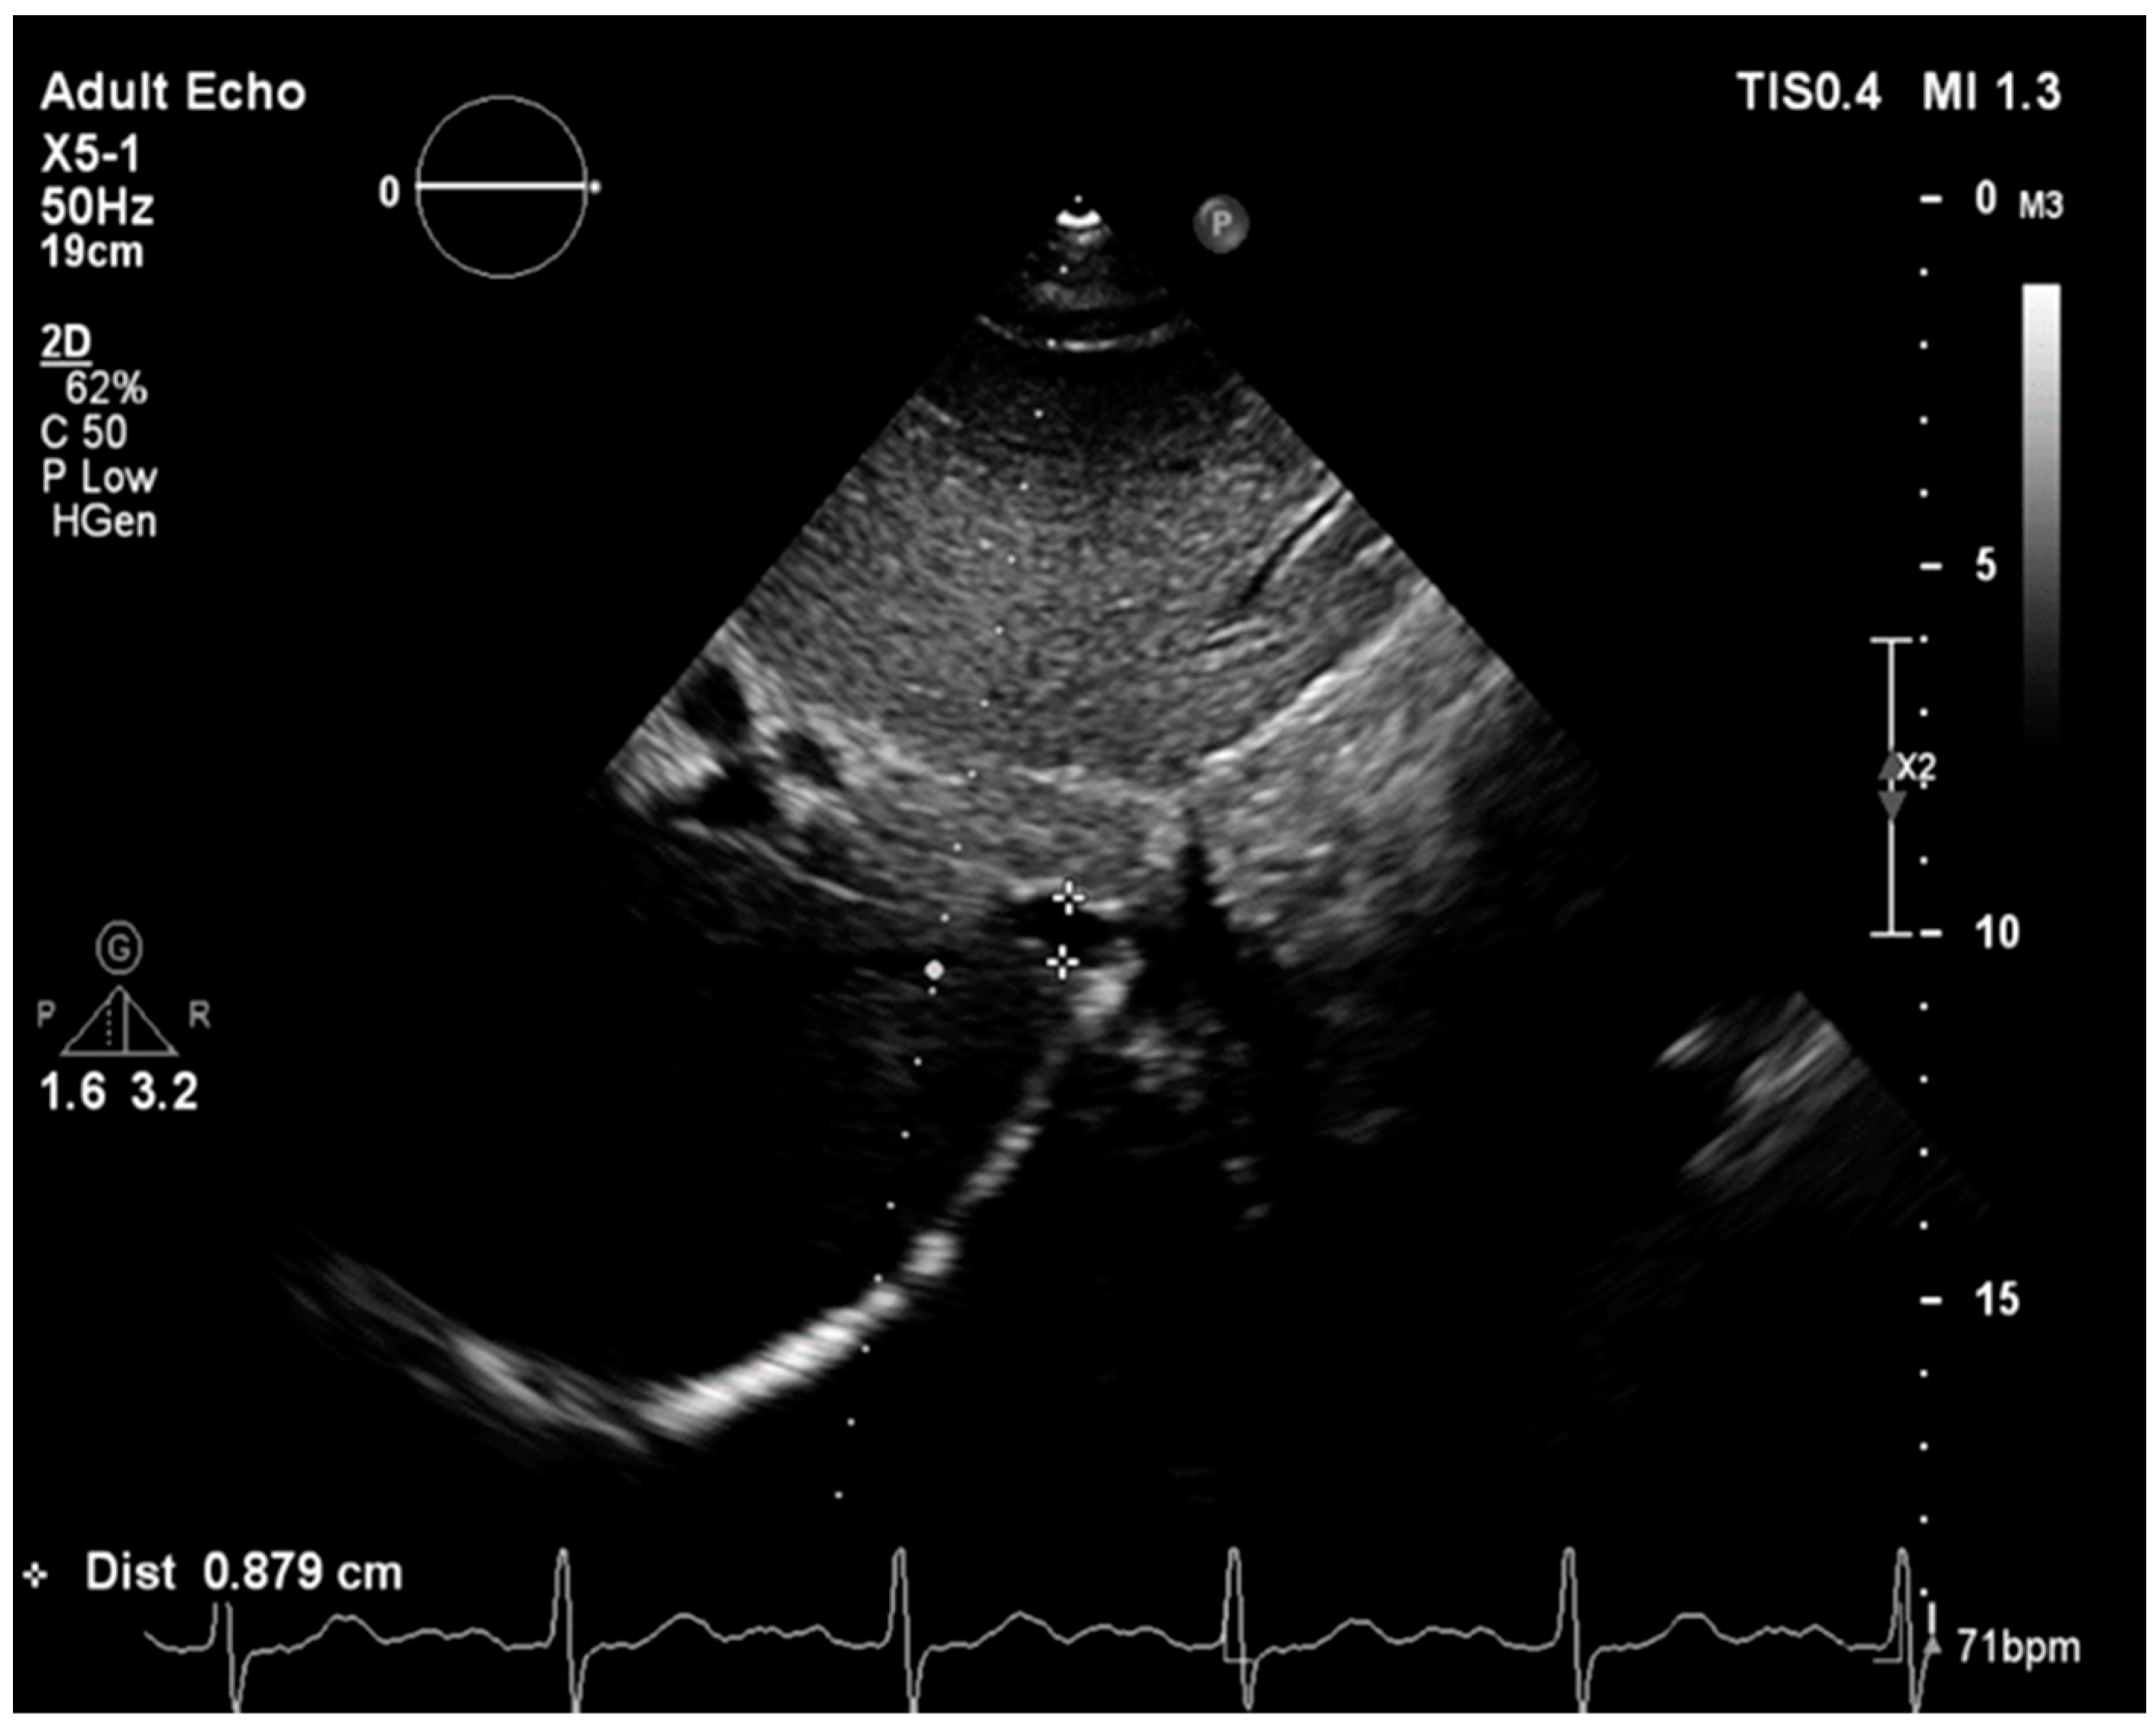

2.2. Echocardiographic Measurements

2.2.1. Probability of Pulmonary Hypertension Assessment